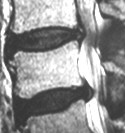

Ursache für die Spinalkanalstenose ist die verschleißbedingte Verschmälerung der Bandscheiben, die zu einer dauerhaften Fehlbeanspruchung und schließlich zur Arthrose der kleinen Wirbelgelenke führt. Die daraus resultierende Verdickung dieser Gelenke und der anliegenden Bänder führt zu einer Einengung des Wirbelkanals und der Nervenaustrittskanäle der Wirbelsäule. Dadurch kommt es zu einer dauerhaften mechanischen Reizung der Nerven. Gleichzeitig werden infolge des Verschleißprozesses chemische Reizstoffe frei, die den chronisch-entzündlichen Prozess im Wirbelkanal verstärken. Die Diagnose wird heutzutage mittels Kernspintomographie gestellt.